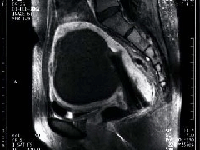

塞栓術治療3日後

黒く抜けているのは全て壊死におちいった筋腫